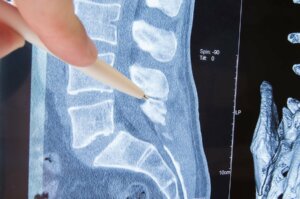

Selkäranka on nikamista koostuva luinen rakenne, jonka tehtävänä on suojata luuydintä ja tarjota meille mahdollisuuden liikkua vapaasti. Nikamien molemmilta puolilta voimme taas löytää niin kutsuttuja välejä, joista lähtee erilaisia selkäydinhermoja, jotka kulkeutuvat puolestaan muihin kehomme osiin.

Sitä selkärangan osaa, joka tulee ulos nikamasta, kutsutaan “hermojuureksi”. Radikulopatia on sairaus, jossa hermo joutuu puristuksiin juuri tässä hermojuuressa ja tästä syystä sitä kutsutaan usein myös hermojuurivaurioksi tai hermojuuritulehdukseksi. Mutta mitkä tähän sairauteen johtavat syyt sitten ovat? Ja mitä kliinisiä oireita tässä taudinkuvassa esiintyy? Tulemme alla vastaamaan kaikkiin näihin kysymyksiin sekä kertomaan samalla hieman enemmän siitä, millaisia hoitomuotoja radiokulopatiaan tänä päivänä on olemassa.